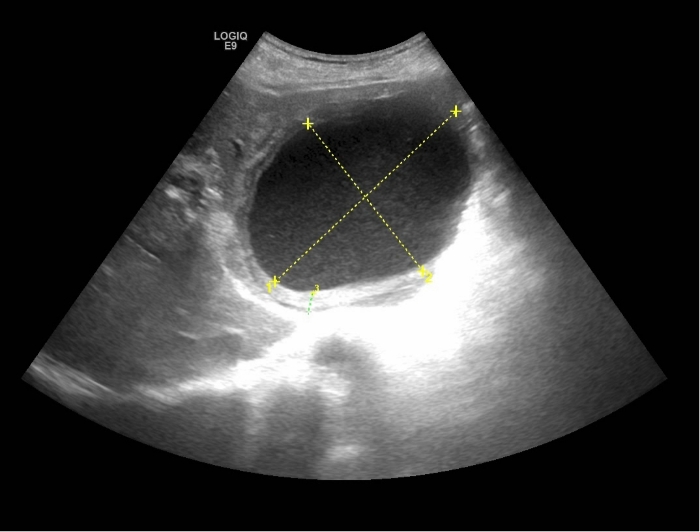

一名73岁的男性,因腹痛、发热4天,来我院消化内科就诊。经查体,患者以中上部腹痛为主,体温最高39.0℃。腹部彩超检查显示,肝左叶可探及大小约108x79mm的巨大囊性回声,挤压周围正常肝组织和血管,内部“灰蒙蒙”的。